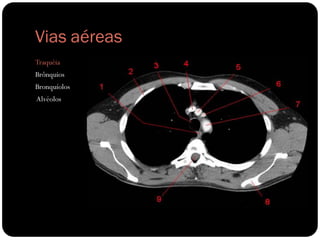

Vias aéreas

Traquéia

Brônquios

Bronquíolos

Alvéolos